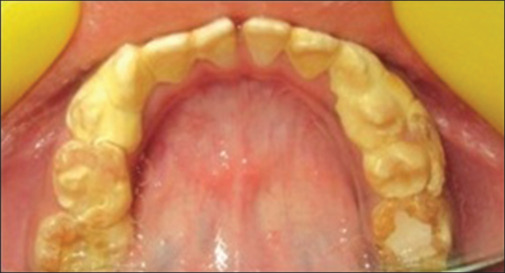

背景:良好的口腔卫生是整体口腔健康的重要组成部分。随着时间的推移,人们开发出了各种方法来评估口腔卫生状况。1960 年,Greene 和 Vermillion 引入了口腔卫生指数 (OHI),对 12 个牙齿表面的碎屑和牙结石进行评估。1964 年,他们提出了简化口腔卫生指数 (OHI-S),该指数只评估 6 颗指数牙的 6 个表面。作者推荐使用 OHI-S,因为它能更快地进行临床评估,但得出的结论是,尽管这两个指数都足够灵敏,但其灵敏度不如 OHI。1987 年,Garg S 引入了改良口腔卫生指数(OHI-M),通过评估每颗完全萌出恒牙的面部(颊/唇)、口腔(腭/舌),特别是咬合面的碎屑和牙结石,提供更全面的评估。OHI-M是准确评估口腔卫生状况的一种可靠而灵敏的方法。目的:本研究旨在使用OHI、OHI-S和OHI-M对口腔卫生状况进行比较评估,并重新验证OHI-M。由一名研究人员进行评分。样本量根据 95% 的置信水平确定。收集到的数据使用 IBM SPSS 统计软件进行分析,并使用皮尔逊相关检验来评估相关性:结果发现,与 OHI(7.13 ± 1.79)和 OHI-S(3.23 ± 0.99)相比,OHI-M 的平均值和标准差最低(2.55 ± 0.82)。这表明,OHI-M 值的变化小于 OHI 和 OHI-S。三个指数之间呈正相关,具有显著的统计学意义(P < 0.001):结论:与 OHI 和 OHI-S 相比,OHI-M 是评估口腔卫生状况最灵敏的评分方法。这些结果进一步证实了 OHI-M 的有效性。

Background: Good oral hygiene is a critical component of overall oral health. Various methods have developed over time to assess oral hygiene status. In 1960, Greene and Vermillion introduced the Oral Hygiene Index (OHI), which assessed debris and calculus on 12 tooth surfaces. In 1964, they proposed a Simplified Oral Hygiene Index (OHI-S), which evaluated only 6 surfaces of six index teeth. The authors recommended the OHI-S due to its faster clinical assessments but concluded that it was less sensitive than the OHI despite both indices being sufficiently sensitive. In 1987, Garg S introduced the Modified Oral Hygiene Index (OHI-M), which provides a more comprehensive evaluation by assessing debris and calculus on the facial (buccal/labial), oral (palatal/lingual), and specifically occlusal surfaces of each fully erupted permanent tooth. The OHI-M is a reliable and sensitive method for accurately evaluating oral hygiene status.